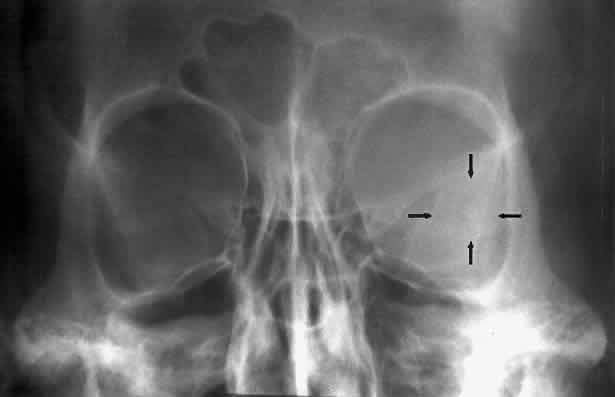

Calcification in the orbit can be seen in retinoblastoma, meningioma, organized hematoma, or a phlebolith associated with venous malformations. Intraocular calcification is seen with tumors such as retinoblastoma or with degenerative changes of the lens, choroid, or vitreous23 (Figs. 10 and 11).

Fig. 10. Caldwell projection of a hemangioma of the left orbit. Soft tissue density is seen in the lateral orbit with partial calcification (arrows).